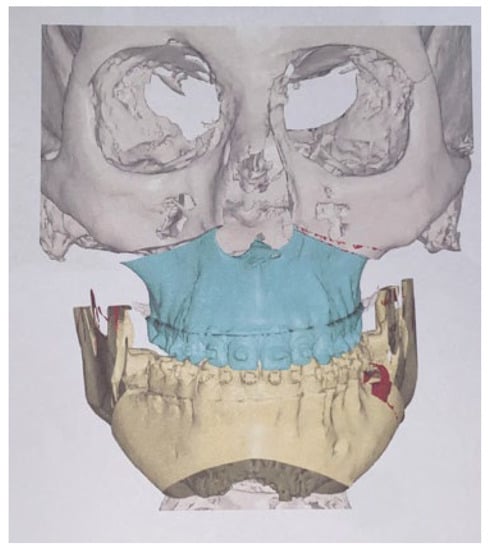

- Three-dimensional-guided and similar planning guides: Cascone et al. introduced the usage of 3D mandible and skull cast models based on CBCT to establish the best methods of surgical planning on 3D printed models [102]. The herein-mentioned planning on two cases indicates that proportional condylectomy might be used as the sole procedure for UCH treatment when detailed measurements on 3D models, either virtual or printed, are used to improve the surgical outcomes [103,104].